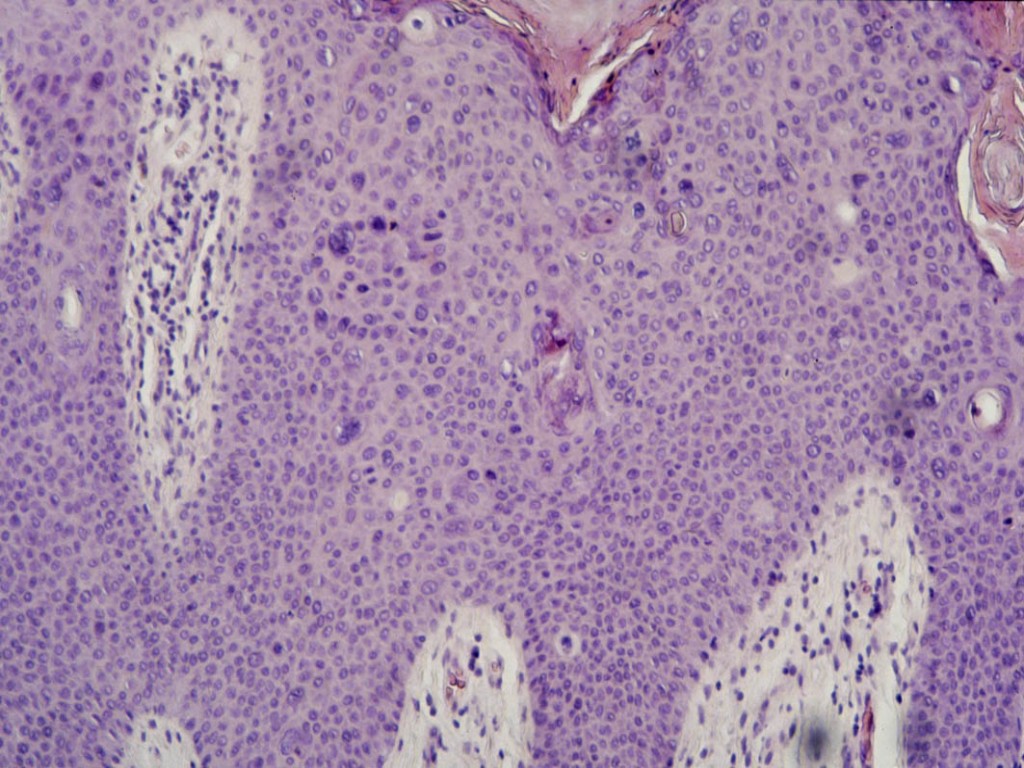

Histologie:M. Bowen

is een intra-epidermaal spinocellulair carcinoom, een 'carcinoma in situ'. In

het sterk acanthotische epitheel ziet men onder een deels hyperkeratotische

deels parakeratotische hoornlaag, hoe wanordelijk de cellen zijn gerangschikt;

er zijn vele kern- en celatypien, irregulaire kernvormen, atypische celdelingen,

reuscellen, pycnotische kernen en individueel verhoornde cellen met pycnotische

kernen (dyskeratose); ook hoornparels komen voor. Het stratum basale is intact

en er is geen infiltratieve groei. Treedt metastasering op dan zijn de basale

laag en de basale membraan wel doorgroeid door de anaplastische cellen en gedraagt

de tumor zich als een spinocellulair carcinoom. Deze doorgroei kan soms pas

na jaren optreden, maar bij m. Queyrat ziet men dit doorgaans veel sneller gebeuren.

In de cutis bestaat een banaal lymfocytair ontstekingsinfiltraat, soms gemengd

met plasmacellen.